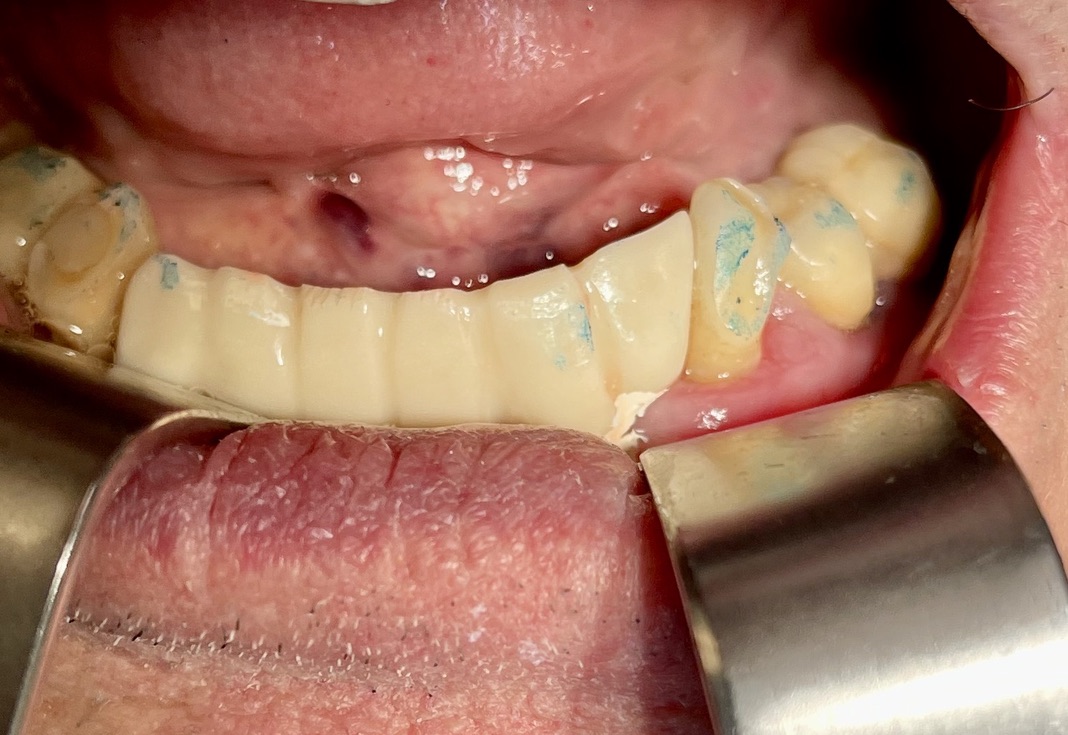

CASO CLINICO : Riabilitazione del 28/04/2021

In particolare considero notevoli i seguenti aspetti:

• 1 età del paziente. 83 anni

• 2 esecuzione dei primi 6 impianti: 25 anni fa

• 3 esecuzione dei 5 impianti successivi: 14 anni fa

• 4 medicinali assunti dal paziente: nessuno

• 5 presenza di impianti in zona tuber/pterigoidea

• 6 presenza di impianti inclinati di antica data

• 7 presenza di impianto piegato in 25. (Per parallelizzarlo)

• 8 presenza di due miniimpianti in 11-12

• 9 presenza di barra saldata nel settore superiore

• 10 grave parodontopatia del settore inferiore

• 11 problematiche igieniche

• 12 insuccesso implantare di impianto di Tramonte inferiore, impianto precedente al 2004, nel quadro della generale parodontopatia

• 13 l’inserimento dei tre impianti non ha comportato innesti di osso o di tessuti connettivali.

• 14 Non ha reso necessari scollamenti

• 15 Non è stata necessario isolare le emergenze dei nervi alveolari inferiori

• 16 Trattandosi di osso ad elevata densità si è ricorsi alla fresa elicoidale, strumento raramente utilizzato da noi perchè non necessario e perchè ci sono zone in cui il suo utilizzo comporta rischi chirurgici per noi non accettabili. Inoltre questa fresa asporta quantità discrete di osso che preferiamo resti dove la natura lo ha messo. Interessante il fatto che il diametro della fresa è di solo 2 mm

• 17 Trattandosi di osso denso, gli impianti utilizzati avevano un diametro di soli 4 mm dopo maschiatura col corrispondente maschiatore.

• 18 Al controllo del 3/5/2021 il paziente non è gonfio e riferisce che mangia finalmente bene.

• 19 Inizio intervento implantare alle 8.45. fine intervento implantare alle 9.36.

• 20 Cementazione del provvisorio, confezionato al momento, ultimata alle 10.30. durata totale permanenza del paziente in ambulatorio1,45 ore.

Le immagini forniscono nelle didascalie ulteriori informazioni.